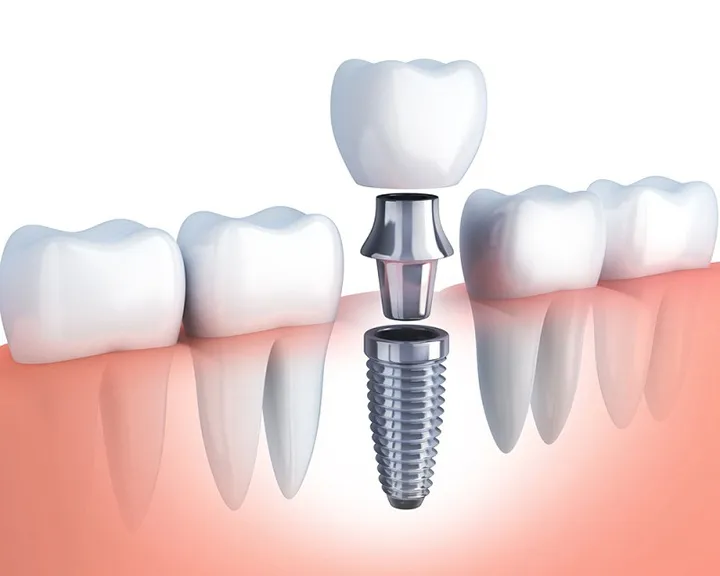

Công nghệ implant ngày càng trở thành lựa chọn ưu tiên trong chăm sóc răng miệng hiện đại, mang lại hiệu quả bền vững và thẩm mỹ

Trong lĩnh vực nha khoa hiện đại, các loại implant đóng vai trò then chốt trong việc phục hồi chức năng răng mất và mang lại nụ